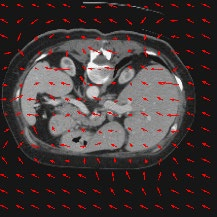

Transformers have made remarkable progress towards modeling long-range dependencies within the medical image analysis domain. However, current transformer-based models suffer from several disadvantages: (1) existing methods fail to capture the important features of the images due to the naive tokenization scheme; (2) the models suffer from information loss because they only consider single-scale feature representations; and (3) the segmentation label maps generated by the models are not accurate enough without considering rich semantic contexts and anatomical textures. In this work, we present CASTformer, a novel type of generative adversarial transformers, for 2D medical image segmentation. First, we take advantage of the pyramid structure to construct multi-scale representations and handle multi-scale variations. We then design a novel class-aware transformer module to better learn the discriminative regions of objects with semantic structures. Lastly, we utilize an adversarial training strategy that boosts segmentation accuracy and correspondingly allows a transformer-based discriminator to capture high-level semantically correlated contents and low-level anatomical features. Our experiments demonstrate that CASTformer dramatically outperforms previous state-of-the-art transformer-based approaches on three benchmarks, obtaining 2.54%-5.88% absolute improvements in Dice over previous models. Further qualitative experiments provide a more detailed picture of the model's inner workings, shed light on the challenges in improved transparency, and demonstrate that transfer learning can greatly improve performance and reduce the size of medical image datasets in training, making CASTformer a strong starting point for downstream medical image analysis tasks.